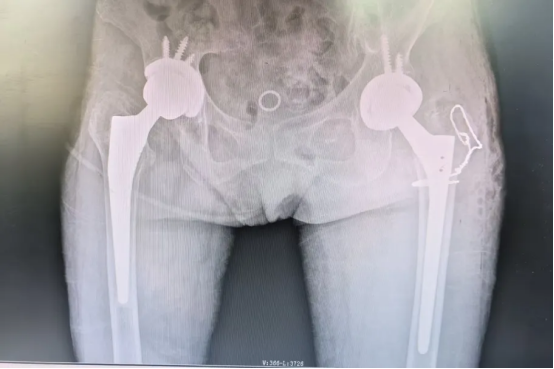

术前摄片